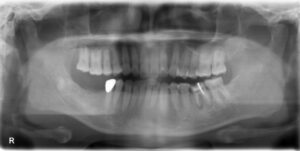

• 下顎大臼歯2本欠損症例

BEFORE AFTER 67歳女性/下2本/インプラント埋込手術 【治療内容】 右下第一大臼歯、第二大臼歯が根っこの先…